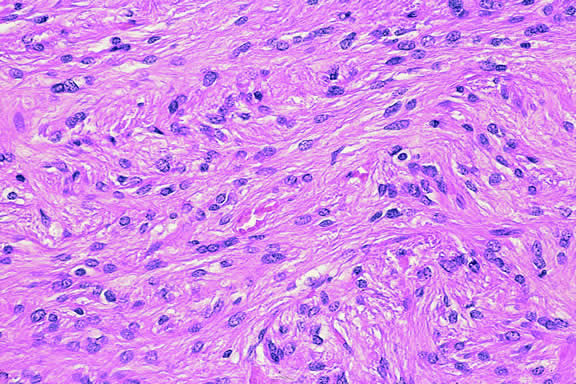

MICROVASCULAR PATTERNS.

Certain microvascular patterns within uveal melanomas have been shown to be prognostic indicators for death from metastatic melanoma.121 Folberg and associates identified nine morphologic patterns of tumor vessels in eyes removed for ciliary body or choroidal melanoma and designated them: (1) normal, (2) silent, (3) straight, (4) parallel, (5) parallel with cross-linking, (6) arcs, (7) arcs with branching, (8) loops, and (9) networks. The presence of vascular loops and microvascular networks composed of back-to-back loops that encircle microdomains of tumor are strongly associated with death from metastatic melanoma122 (Fig. 45). Prognostic vascular patterns appear to be consistent throughout the depth of a tumor, and the cross-sectional area occupied by prognostic microvascular patterns also has prognostic value.123,124 Additional studies from Folberg's laboratory have compared the microcirculation architecture of nevi and melanomas125 and examined the relationship between microvascular architecture and the aggressive behavior of ciliary body melanomas.126 Attempts to detect prognostically significant microcirculatory patterns in vivo using noninvasive imaging techniques including ultrasonography127,128 and confocal angiography with fluorescein or indocyanine green have been made.129,130 A study of 496 posterior uveal melanomas at the AFIP confirmed that the presence of loops did indicate poor outcome but was not as good a prognostic indicator as the mean diameter of the largest nucleoli, cell type, or tumor size.131

Fig. 45. Networks of vascular loops, uveal melanoma. Fibrovascular septa divide parts of this predominantly epithelioid melanoma into roughly circular zones called vascular loops. Vascular networks are composed of adjacent vascular loops. Uveal melanomas that contain vascular loops and networks have a poorer prognosis. (Hematoxylin-eosin, × 50.)